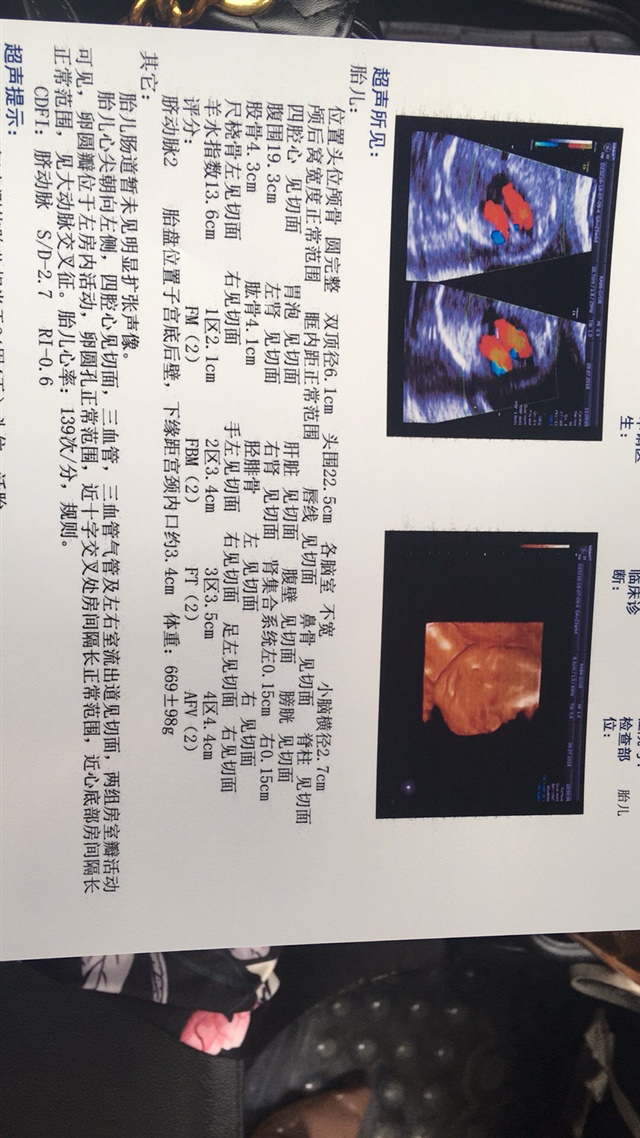

可乐双胞胎兄弟

2018-06-01

2736 人回复